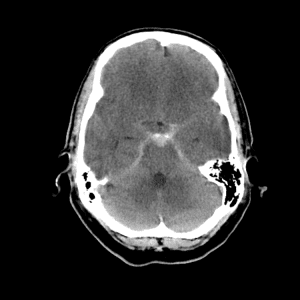

Basilar artery thrombosis